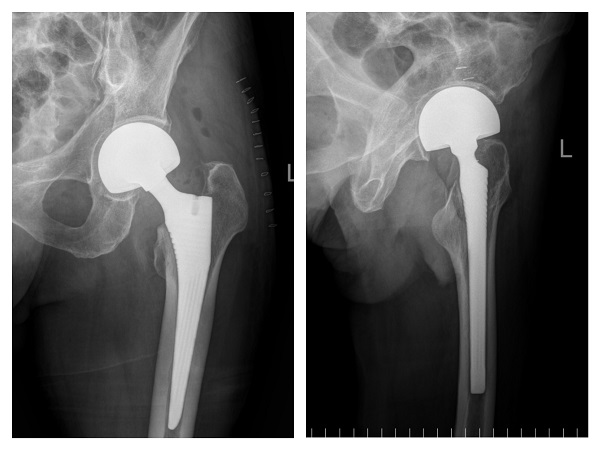

入院一周后,肺部感染逐渐得到控制,氧饱和度正常后,潘主任团队为许爷爷进行左侧人工股骨头置换术,手术十分顺利。术后,科室医护人员密切关注老人的神志、呼吸和各项生命体征变化,及时根据病情变化调整治疗方案,并加强肺功能锻炼。术后三天,许爷爷能够在助行器辅助下下床行走,无明显不适,生命体征平稳。在科室医护团队日夜精心的照料下,许爷爷日见好转,说话声音开始响亮,浑身也有了力气,其家属表示深深地感谢,经过半个多月的精心治疗,许爷爷现已康复出院。